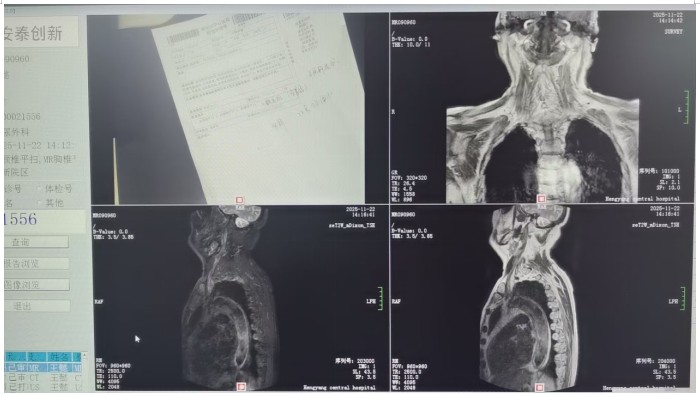

馬子芳團(tuán)隊(duì)詳細(xì)詢問(wèn)患者病史和治療情況后,對(duì)患者進(jìn)行了相關(guān)輔助檢查,初步診斷患者為神經(jīng)源性膀胱??紤]到老人82歲高齡、基礎(chǔ)疾病多等情況,團(tuán)隊(duì)多次組織病例討論,與患者及家屬充分溝通,最終決定為患者實(shí)施微創(chuàng)、可逆的骶神經(jīng)刺激器植入術(shù)進(jìn)行治療。很快,馬子芳團(tuán)隊(duì)為老人實(shí)施了一期骶神經(jīng)調(diào)控電極植入術(shù),術(shù)中精準(zhǔn)定位,成功穿刺骶3神經(jīng)孔,術(shù)中測(cè)試各位點(diǎn)的運(yùn)動(dòng)應(yīng)答、感覺應(yīng)答明顯,無(wú)不良反應(yīng)。